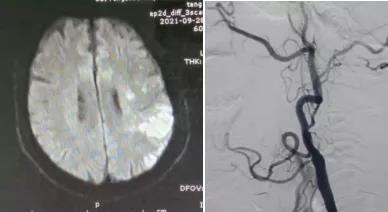

患者男,66歲,因“言語不清1天”于9月27日由外院轉入我院。既往“高血壓病”病史10余年,“冠心病心絞痛”病史2年。患者入院后頸部血管彩超檢查示:左側頸內動脈閉塞;腦MRI檢查示:左側半球急性腦梗死。10月5日行全腦血管造影檢查示:左側頸內動脈起始處閉塞。考慮患者有急性梗死,血管再通治療容易出現過度灌注綜合征引起腦出血,建議3周后行閉塞再通治療。

10月27日,在局部麻醉下行介入再通治療,腦血管造影示左側頸內動脈起始處閉塞,微導絲攜1.5*2mm球囊多次嘗試,成功通過閉塞段,給予球囊擴張,擴張后造影見有細血流通過,保護傘緩慢通過狹窄段,釋放保護傘,給予4*20mm球囊再次擴張,然后植入閉環支架一枚,造影示血流通暢,顱內血管顯影良好,再通成功,結束手術,患者無不適,3天后出院。